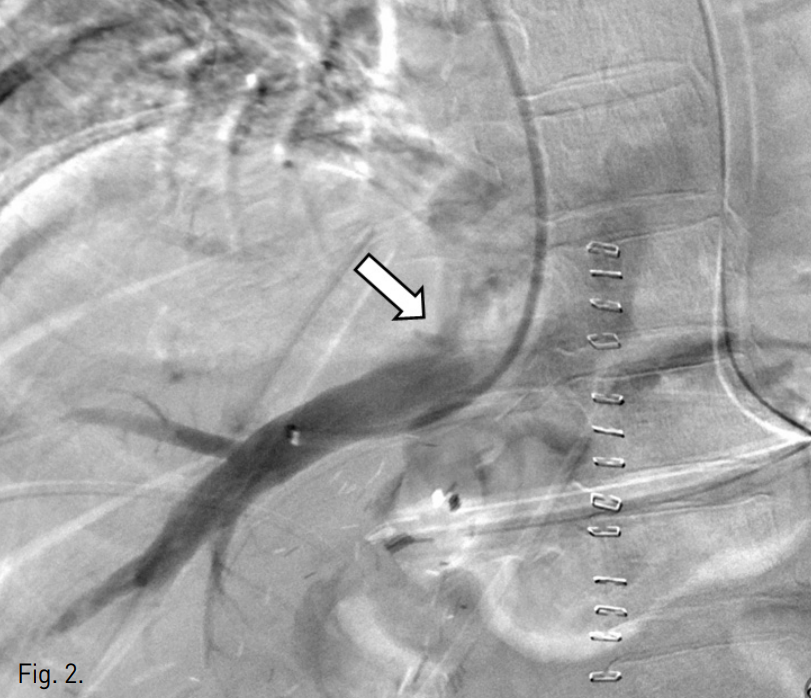

수술 후 1일 째 시행한 color doppler 검사에서 오른간 정맥의 spectral waveform이 monophasic하여 hepatic outflow의 장애가 의심되었다. Liver CT에서 오른간정맥의 기시부가 좁아져 있었으며(Fig. 1) 인접한 아래대정맥 내에 소량의 혈전이 의심되었다. 정맥조영술을 시행하였으며 오른간정맥과 아래대정맥 사이의 관강내(intraluminal) 협착 소견을 확인할 수 있었다(Fig. 2).

Fig. 2

Right hepatic venogram shows a filling defect of the right hepatic vein-IVC anastomotic site (arrow).